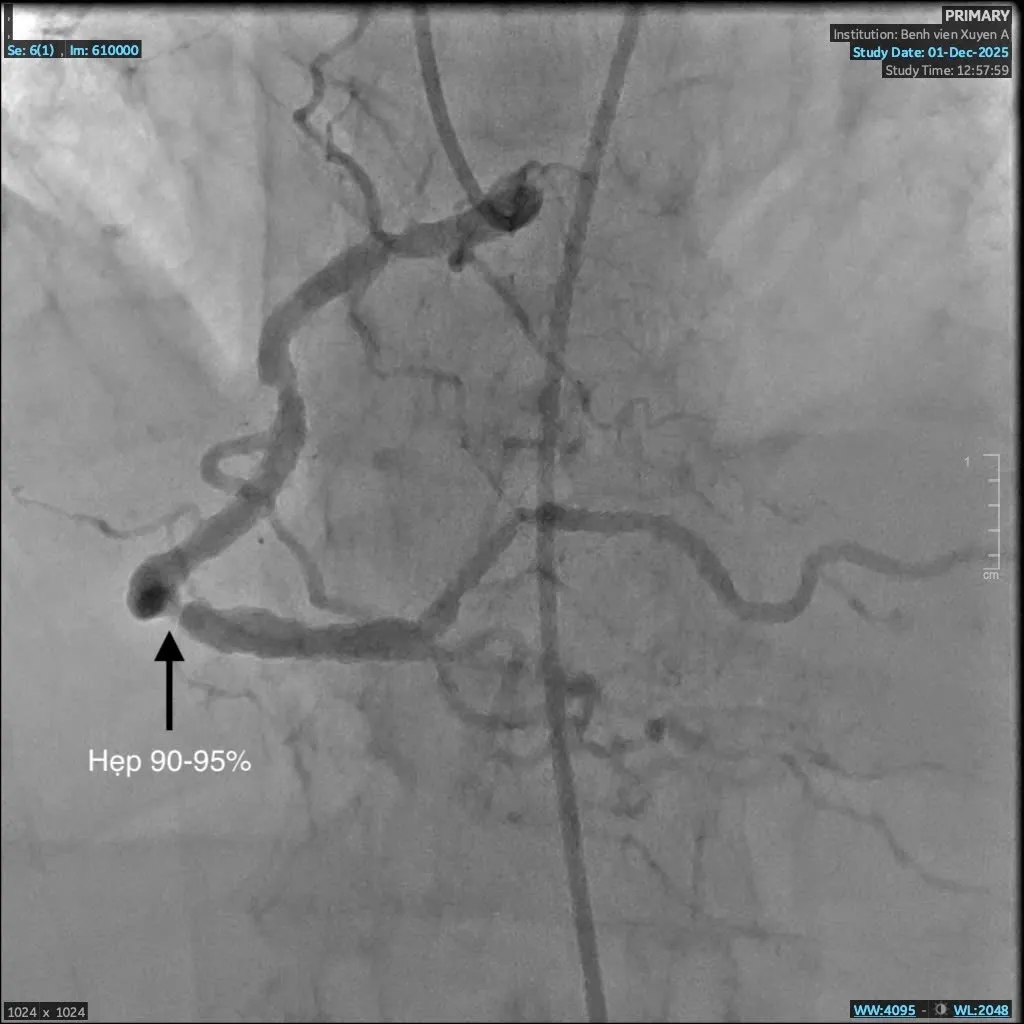

Mạch máu trước can thiệp hẹp đến 95%

Ngay khi tiếp nhận, các bác sĩ khoa Cấp Cứu đã thăm khám và ban đầu xác định bệnh nhân bị phù phổi cấp. Người bệnh được chuyển lên khoa Hồi Sức Tích Cực để điều trị ổn định tình trạng suy hô hấp, sau đó chuyển bệnh nhân lên phòng DSA chụp mạch máu nuôi tim kiểm tra tình trạng tim mạch. Kết quả chụp động mạch vành phát hiện bà C. bị hẹp nặng ba nhánh mạch vành, rơi vào nguy kịch nhồi máu cơ tim. Đây là nguyên nhân chính khiến bà khó thở, đau nặng ngực.

Bác sĩ Giản Tư Trí - khoa Can Thiệp Tim Mạch Bệnh viện đa khoa Xuyên Á cho biết: “Bệnh nhân C. có tiền căn hen phế quản vào viện trong tình trạng suy hô hấp, việc chẩn đoán gặp nhiều khó khăn. Trong quá trình can thiệp, dưới hướng dẫn của hệ thống số hóa xóa nền DSA, ê-kíp nhận thấy mạch vành của bệnh nhân bị vôi hóa nhiều do đái tháo đường, suy thận lâu năm. Vôi hóa là “kẻ thù” của can thiệp mạch vành, gây khó khăn cho việc nong và đặt stent, thậm chí khiến việc can thiệp thất bại. Nhưng với sự tỉ mỉ và kinh nghiệm xử trí nhiều ca đặt stent phức tạp trước đó, các bác sĩ khoa Can Thiệp Tim Mạch đã vượt qua thách thức và đặt stent thành công, tái thông mạch máu nuôi tim, cứu bà C. qua cơn nguy kịch.”